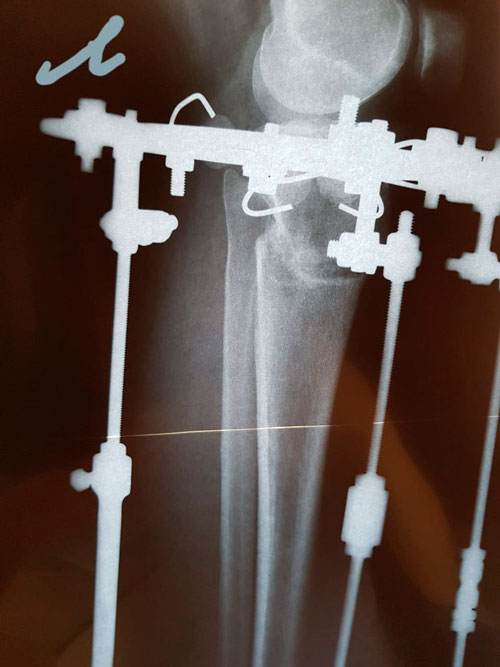

Исходник - 31 год.

Дата операции - 28.02.2019г.

Ротация с обеих сторон 30 градусов.

рентген в 65 дней.

рентген в 86 дней!

рентген в 86 дней.